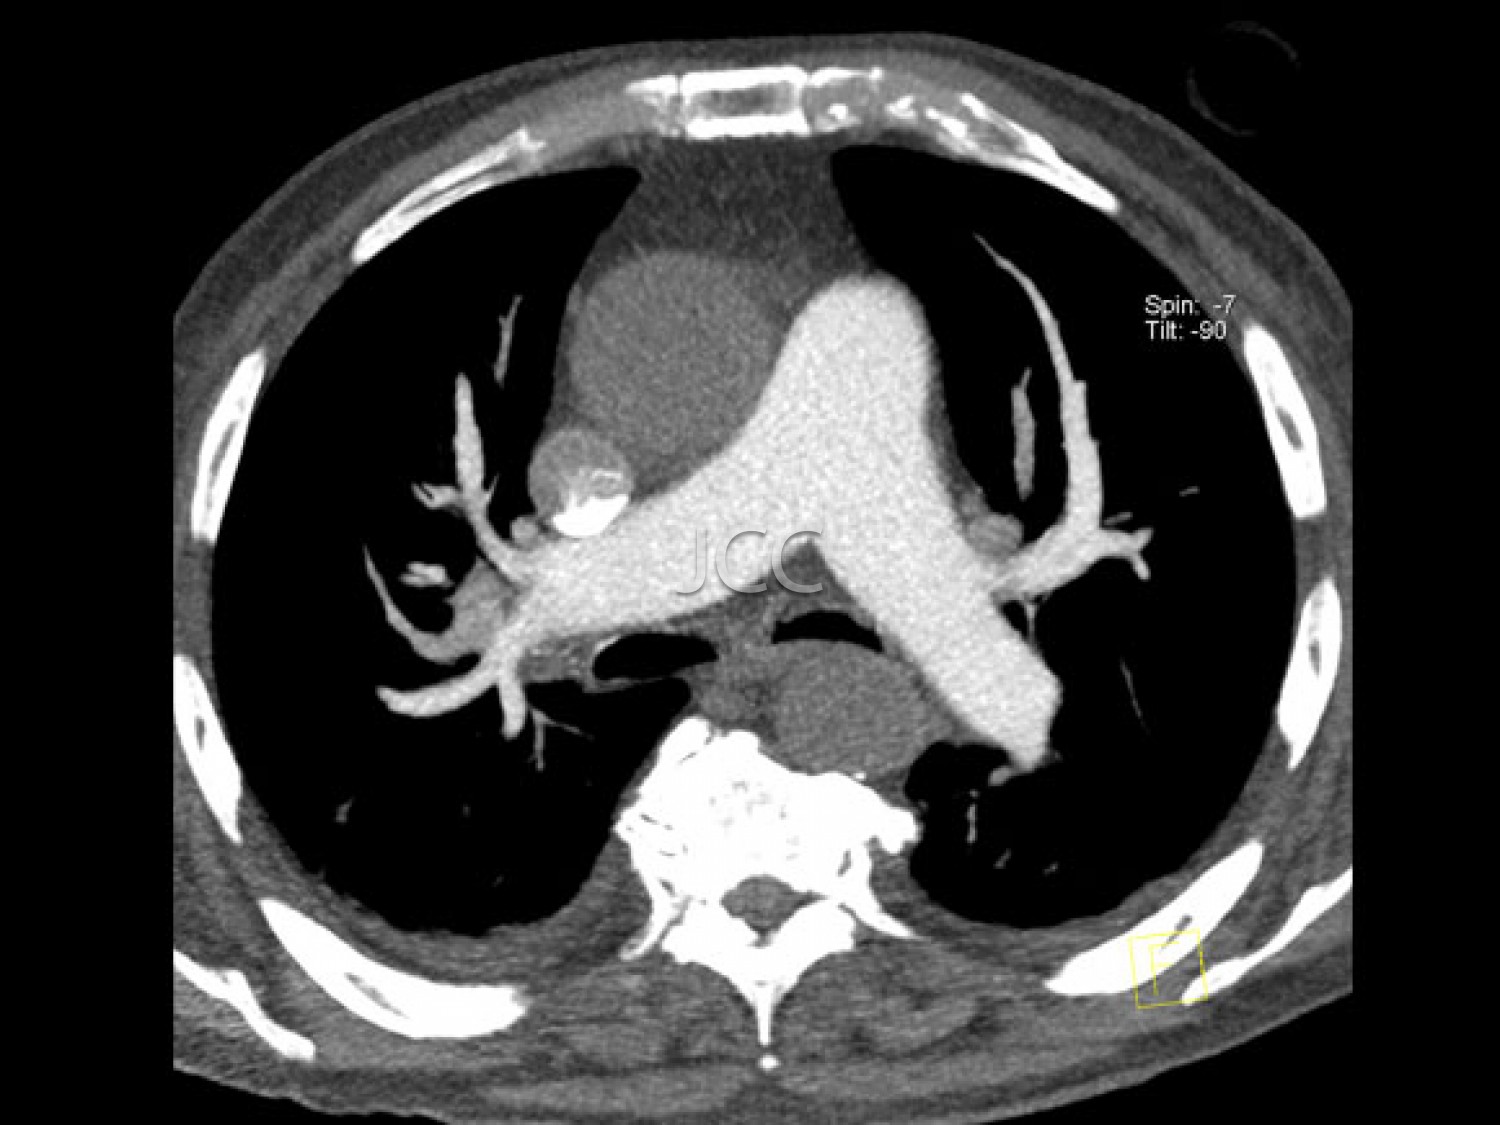

A introdução dos mais recentes sistemas de tomografia computorizada Dual-Source, primeiros equipamentos destes instalados em Portugal – Siemens Somaton Definition FLASH e DRIVE, com dupla ampola e duplo detector, permite a aquisição de 256 imagens em 0.28 segundos, utilizando-se uma dose de radiação muito reduzida, bastante inferior à utilizada, nomeadamente nos equipamentos de 64 cortes, geralmente utilizados para avaliação cardíaca, nomeadamente das artérias coronárias. Associamos ao nosso programa de rastreio a última tecnologia em ressonância magnética 3 tesla para despiste de patologias cerebral, prostática e mamária.

IMAGEM PREVENTIVA

Pela 1ª vez na história da medicina, através da tecnologia multi-detector, com dupla ampola e ressonância magnética de última geração 3 tesla, é possível, de modo não invasivo e capacidade diagnóstica comprovada, efectuar o screening de processos patológicos, para prevenção de doença cardíaca, neoplasias e acidente vascular cerebral – AVC. Salienta-se que com o nosso equipamento de TAC dual source - 256 cortes -  a dose de radiação é  muito baixa (cerca de 10 vezes inferior à dose dos equipamenos de TAC de 64 cortes).  Os dados obtidos nestes equipamentos de ultima geração são tratados em estações de trabalho de alto nível, que utilizando sistemas CAD e de visualização tridimensional, resulta em informação detalhada e muito rigorosa.

CHECK-UP CARDIO-TORÁCICO

• Angio TC das Coronárias

• TC do Tórax

• TC do Tórax com contraste - Pesquisa de nódulos pulmonares e Avaliação do mediastino